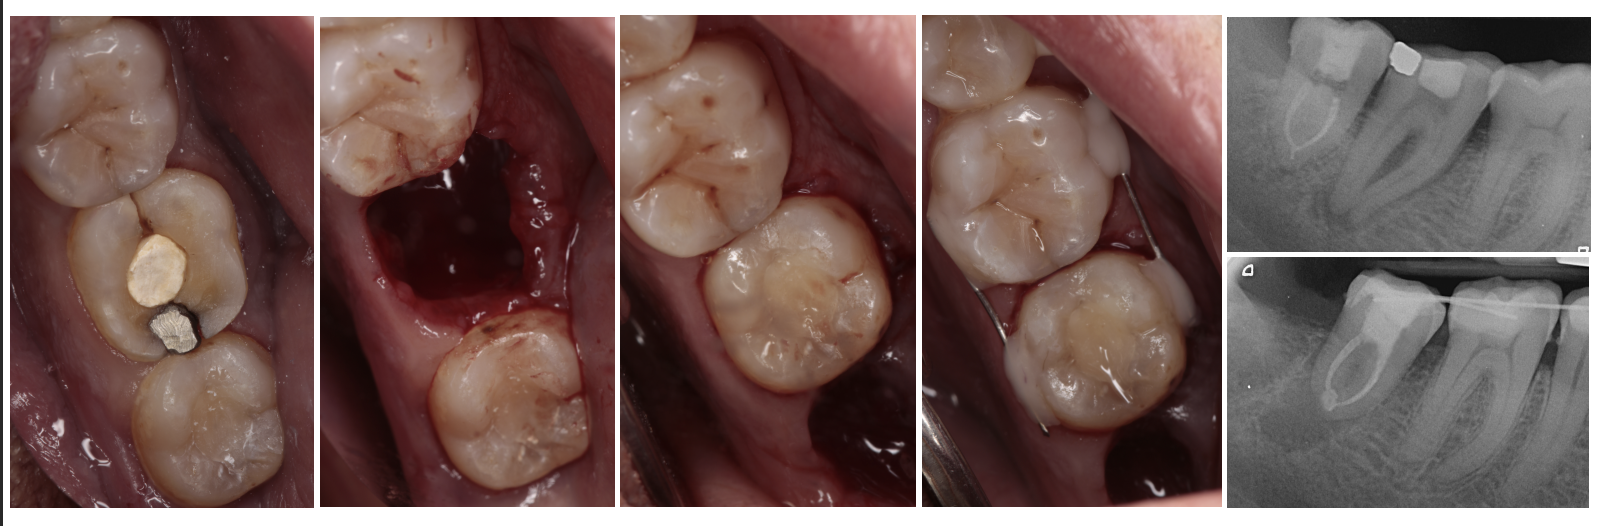

Autotrasplante

Consiste en la movilización de un diente al alvéolo de un diente que ha sido previamente extraído, estando indicado en pacientes en jóvenes y en crecimiento.